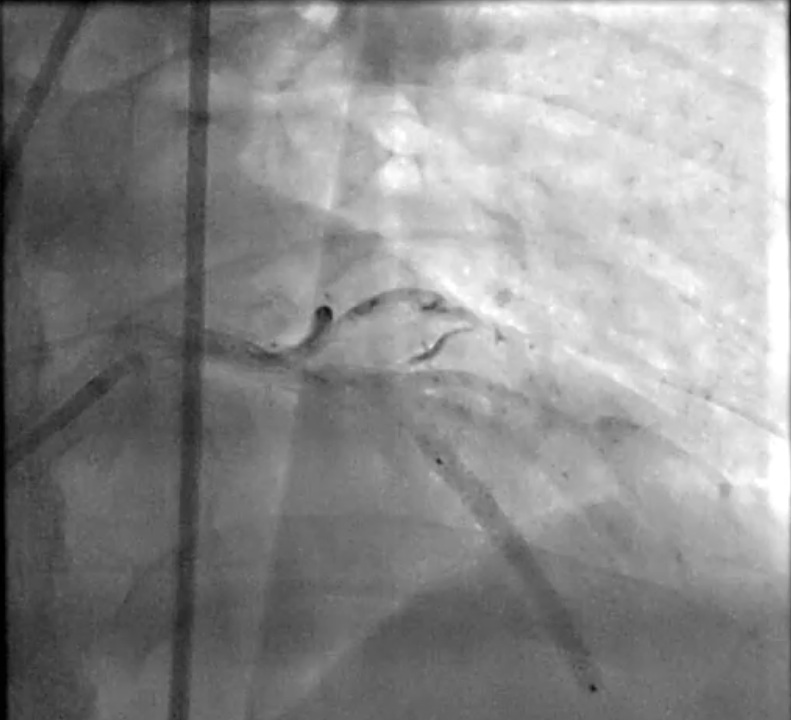

LAD : total occlusion LAD stent thrombosis.